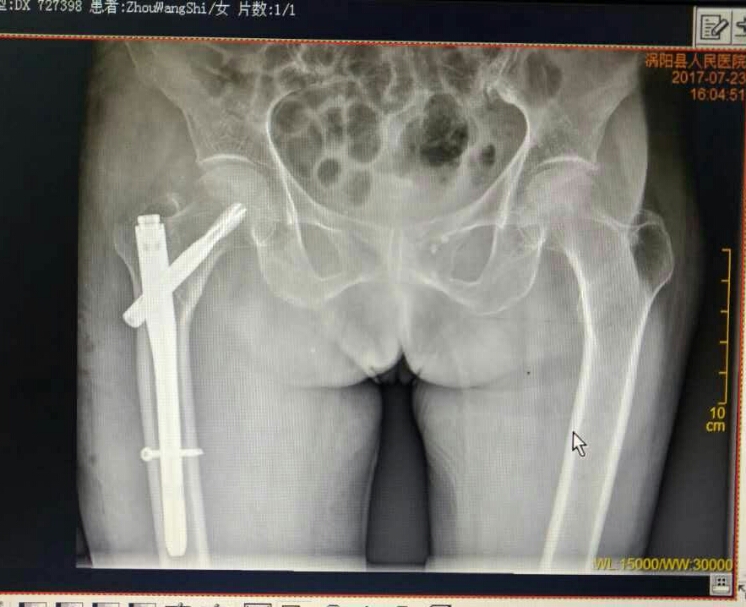

7月17日晚上,家住楚店镇周东村的王奶奶不慎在家摔倒,腿部剧烈疼痛,不能站立和行走,家人急忙将老人送至我院救治,经诊断为右股骨粗隆间骨折,需要住院治疗。副主任医师王洪灵为老人进行了详细的检查,发现患者不仅右股骨粗隆间骨折,还伴有严重的骨质疏松症,且老人年岁已高,身体各项机能退化,手术治疗存在很大的风险性,但是成功后老人就能重新站起来。为慎重起见,骨一科为患者拟定了详细的治疗方案和各种预案,经过充分的术前准备后,于7月20日下午在硬膜外麻醉下为百岁老人行右股骨粗隆间骨折闭合复位PFNA内固定术,手术在主任王海洋的指导下,由副主任医师王洪灵主刀,副主任医师柴林涛协助开展。凭着娴熟的业务技术和充分的术前准备,在相关科室的密切配合下,手术团队仅用40分钟便成功为老人完成手术。术后,在我院骨一科医护人员的精心治疗和护理下,老人恢复较好,7月24日顺利出院,患者及其家人非常满意,对我院骨一科的精湛医术和精心照料赞不绝口。